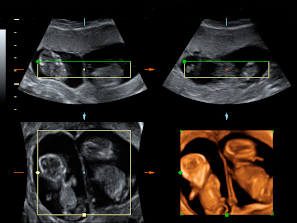

Ecografía en 2D y 3D de gemelos de 11 semanas en planos diferentes

Imágen en dos dimensiones de un embarazo gemelar. El ecografista toma una "porción de imagen" (rectángulos) y luego otro corte o plano diferente (cuadrado), que corresponde a imágenes en 2D y 3D. Podemos observar con gran nitidez a los gemelos en dos bolsas independientes, así como las placentas que los alimentan. La membrana de separación entre ambos hermanos es muy gruesa. El punto central de color que aparece en las ecografías en dos dimensiones (2D) corresponde con la membrana de separación de los gemelos. La imagen en 3D lo confirma sin género de duda.